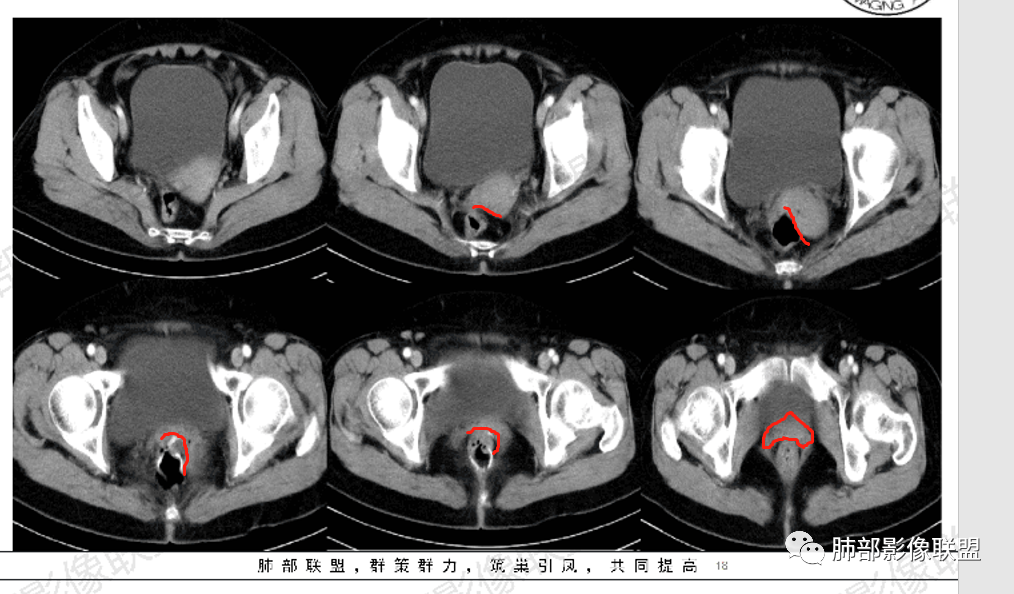

△直肠术区壁增厚,外壁欠清,局部强化偏低,转移瘤确实要考虑

△宫颈局部确实有受压的迹象

△直肠术区局部肠壁增厚了,增强局部有低强化灶,直肠确实符合复发的表现,还是要恶性首选